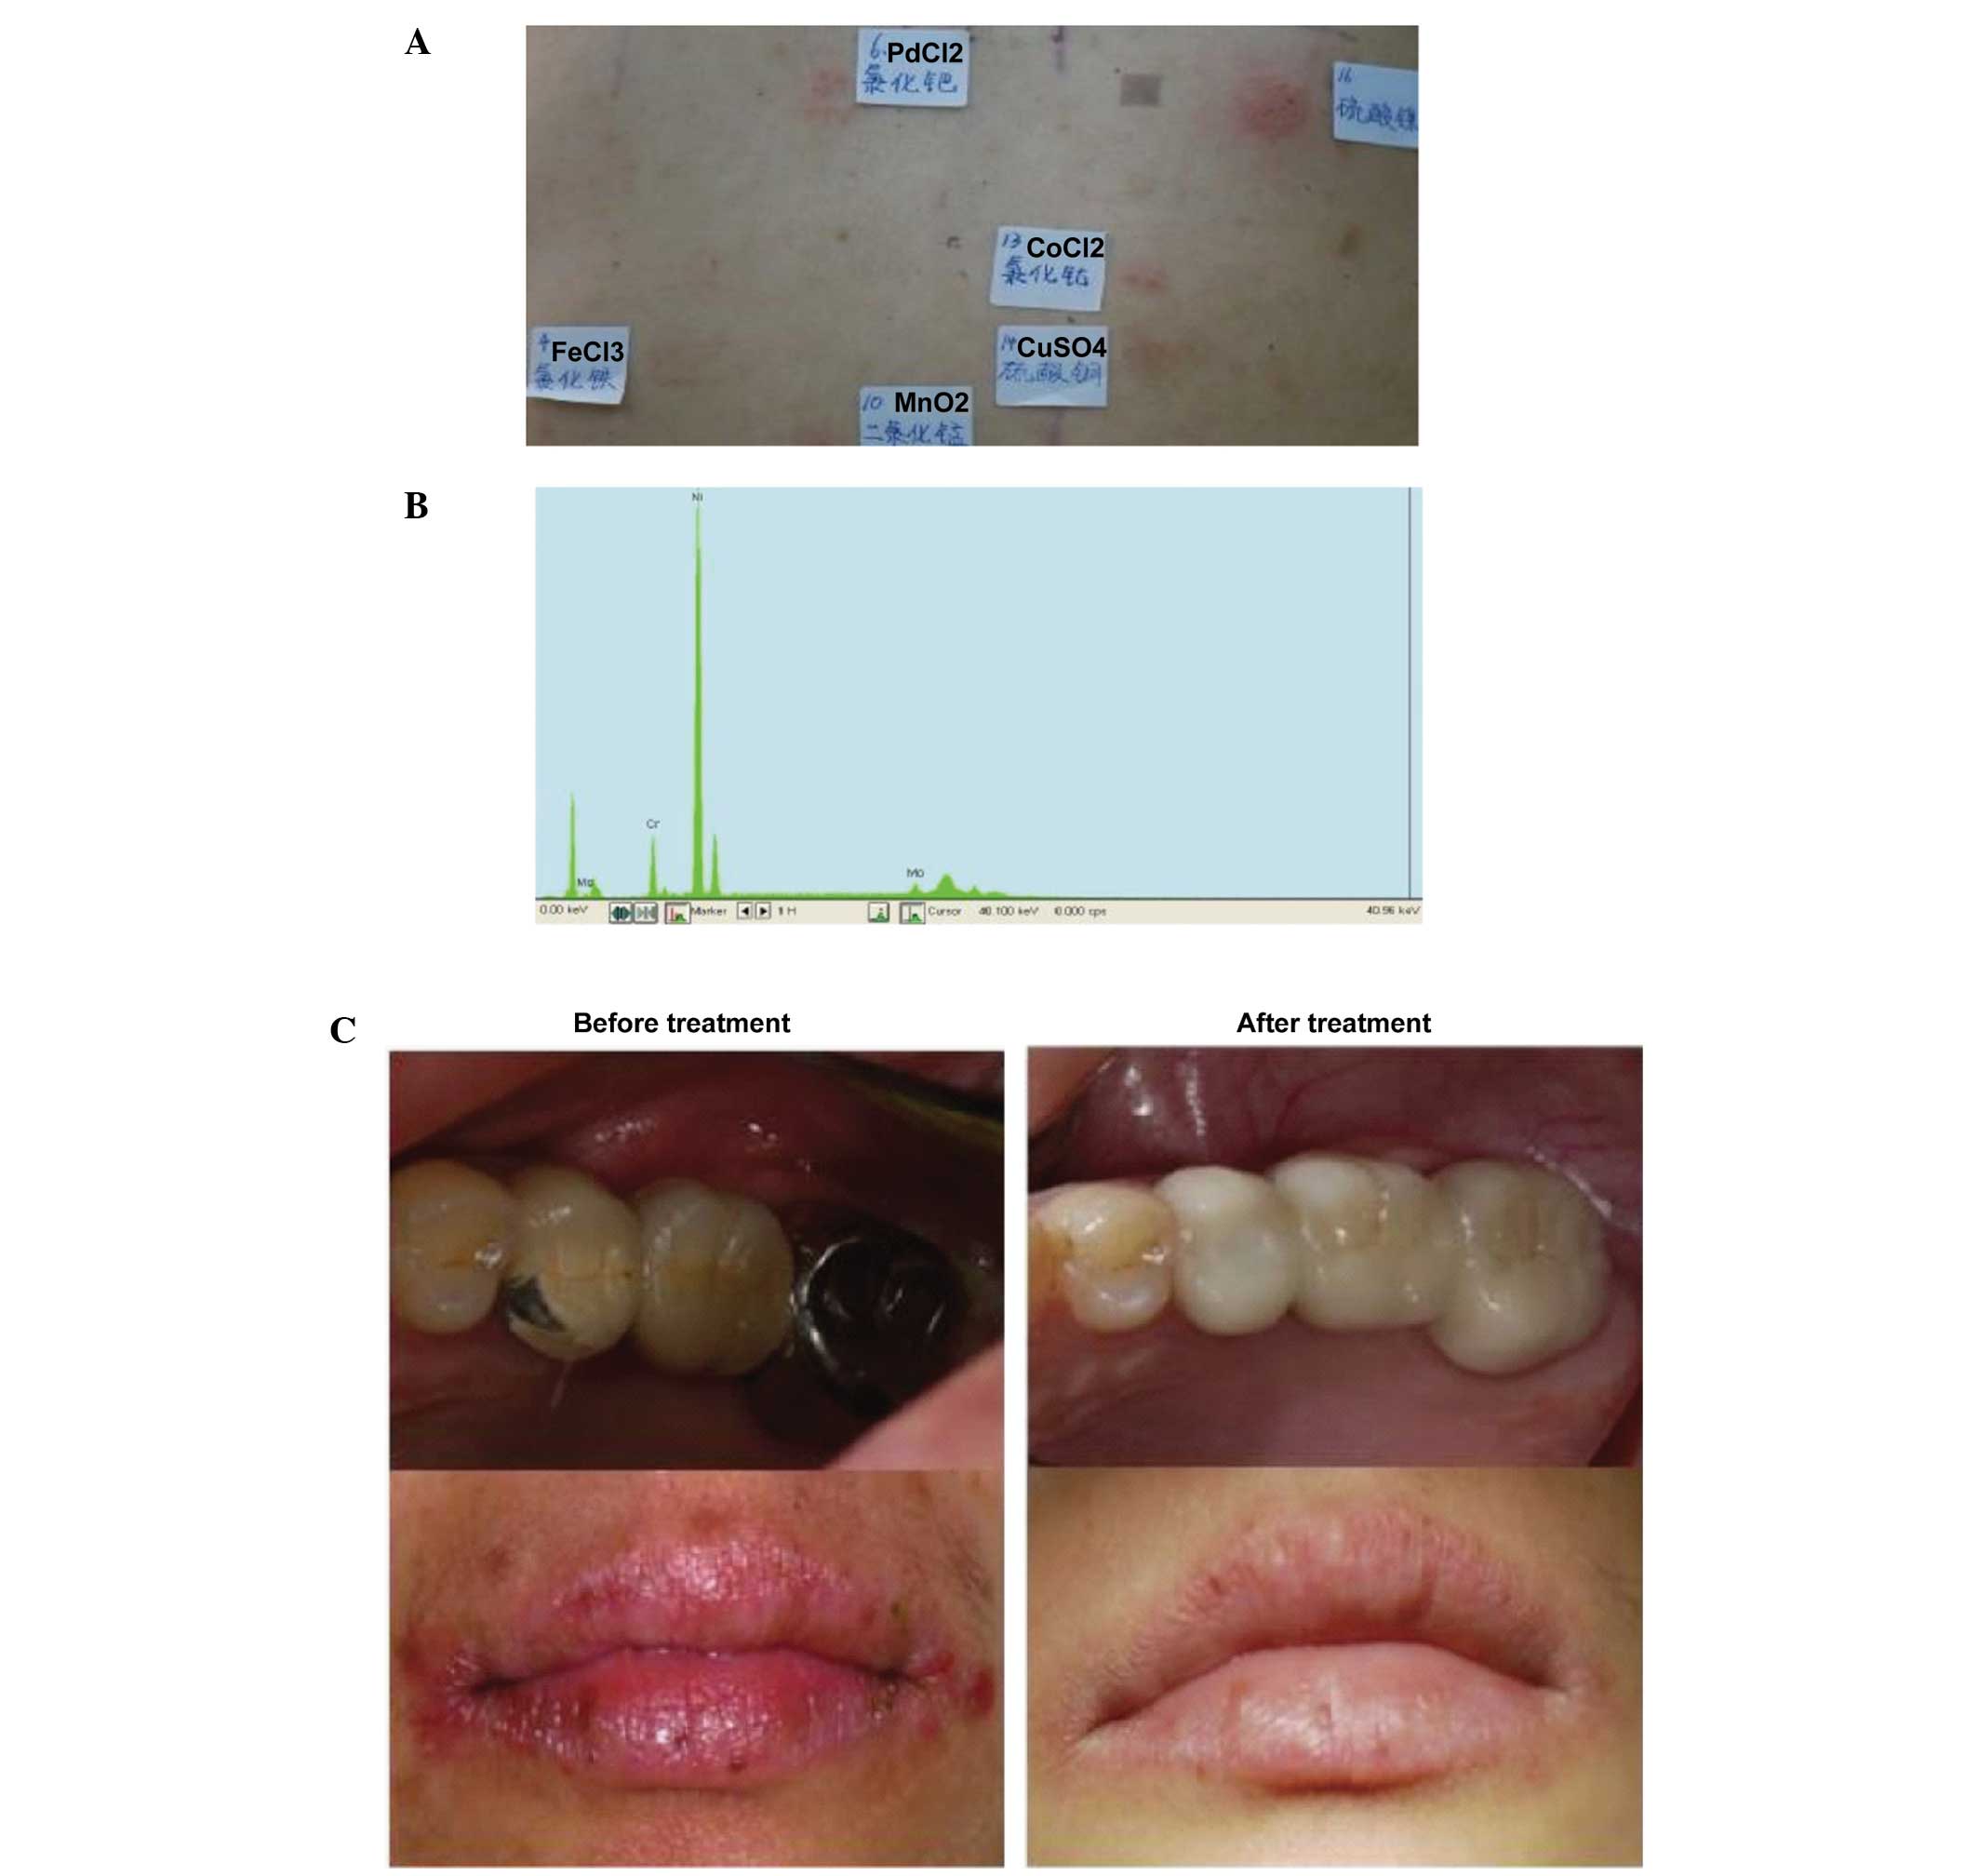

A Comparative Analysis Of Metal Allergens Associated With Dental Alloy

www.spandidos-publications.com

www.spandidos-publications.com

metal allergy dental comparative prostheses alloy allergens gingival hla associated expression tissue analysis dr mmr case